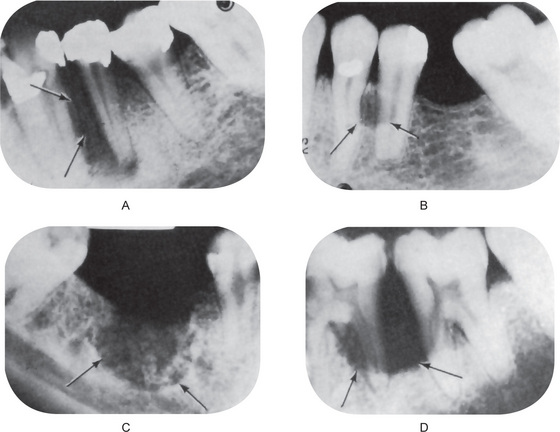

The osteoblastic phase of osteitis deformans is the more commonly recognized one and inevitably occurs regardless of pre-existing osteolytic lesions. The osteoblastic areas, which appear as opacities in the radiograph, tend to be patchy in distribution, eventually becoming confluent, but often still showing minute areas of variation in radiodensity. This patchiness has been termed a ‘cotton-wool’ appearance and is especially well demonstrated in the skull and jaws (Fig. 17-31A).

Figure 17-31 Osteitis deformans.

The radiographs of the skull (A) and the jaws (B) demonstrate the typical ‘cotton-wool’ appearance. (A, Courtesy of Dr John A Campbell)

Radiographs of the jaws may demonstrate even very early phases of the disease, although such phases may not be so specific as to be pathognomonic. An excellent description of the oral manifestations of early osteitis deformans has been provided by Spilka and Callahan. In such cases, poorly defined areas of osteoporosis may be noted, although of more diagnostic significance is the finding of loss of normal trabeculation and the appearance of irregular osteoblastic activity, again giving rise to the typical cotton-wool appearances of ‘Paget’s bone’ (Fig. 17-31B). Although the disease is usually bilateral, it may show radiographic evidence of only unilateral involvement of the jaw, especially early in the course of the disease. This may closely simulate chronic, diffuse, sclerosing osteomyelitis.

The teeth themselves and adjacent bone present significant radiographic changes suggestive of osteitis deformans also. These consist characteristically of a rather pronounced hypercementosis, and often, loss of a well-defined lamina dura around the teeth. Root resorption has been reported in some cases, but this is unusual.